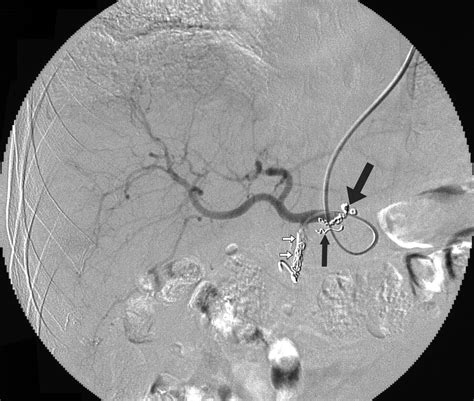

• Digital Subtraction Angiography (DSA): DSA is an invasive procedure that involves injecting a contrast agent into the blood vessels and using X-ray imaging to visualize the vascular anatomy. It is often used in interventional radiology procedures to guide embolization or other treatments.

One of the most common interventional radiology procedures involving the LGA is embolization. Embolization involves blocking the blood supply to a tumor or bleeding site to reduce its size or stop the bleeding. This procedure can be performed using various embolic agents, such as coils, particles, or liquid embolic agents.

Embolization of the LGA is often used in the treatment of gastric cancer to reduce the tumor's blood supply and facilitate surgical resection or other treatments. It can also be used to manage gastrointestinal bleeding, particularly in cases where the bleeding site is difficult to access surgically.